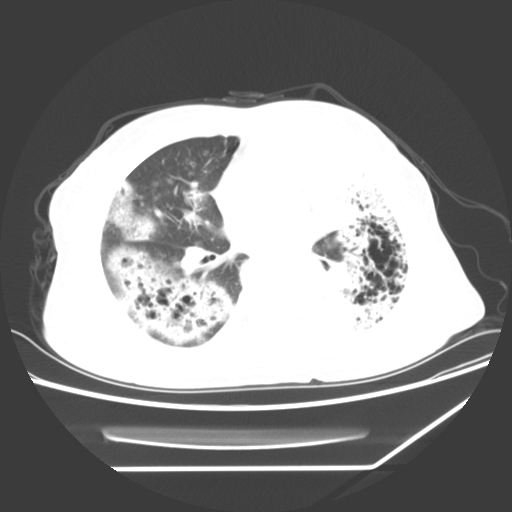

标题: CT25393:病人45岁,咳嗽,吐黄痰带血丝,发热,胸闷月余 [打印本页]

标题: CT25393:病人45岁,咳嗽,吐黄痰带血丝,发热,胸闷月余

1、左肺中央型肺癌并双肺弥漫性转移   2、双肺部感染    3、肺大泡     4、左侧胸腔积液

双侧肺弥漫性病变,可见“空泡征”及“蜂窝征”,考虑肺泡癌可能性大,左侧胸腔积液,考虑胸膜受累可能!

1)不排除肺泡癌可能。2)左侧胸腔积液。